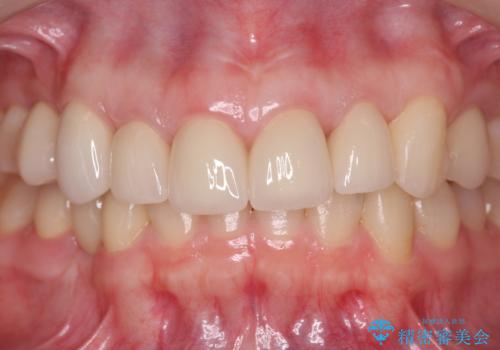

まず虫歯を拡大鏡、マイクロスコープ下で丁寧に取り除き歯肉縁下の虫歯を歯周外科により解決したのち、ジルコニアクラウン製作を行っていきます。

丁寧な虫歯の除去・歯周組織の整備、適合の良い精密なセラミッククラウンの製作といった丁寧な治療の積み重ねが良好な治療結果を得ることにつながります。